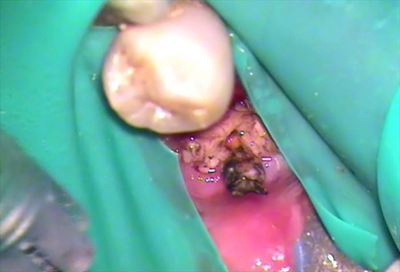

顕微鏡画像です。

根管充填材であるガッタパーチャが突出しています。

水洗しますと、かつて歯であった部分がかなり崩壊しました。

水洗を終えた状態です。

蝕検知液で染色したとすればかなり染まると考えられます。